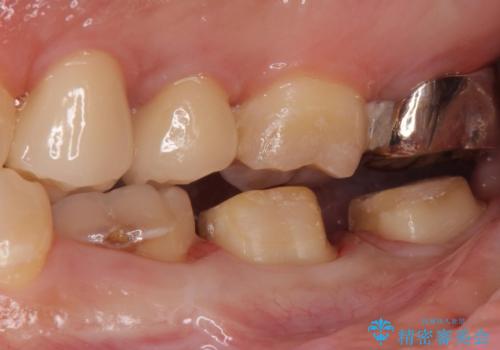

- 口の中を予算の範囲内でできるだけきれいにしたいとのことで来院された患者様です。

矯正治療と虫歯治療を組み合わせてご提案しましたが、ご予算との兼ね合いで虫歯治療のみを行うこととなりました。

奥歯は十分な歯の高さがなかったため、クラウンをかぶせる前に歯周外科治療で歯の高さを出しています。

歯科に通うようになってから磨き残しの状態も改善されていきました。